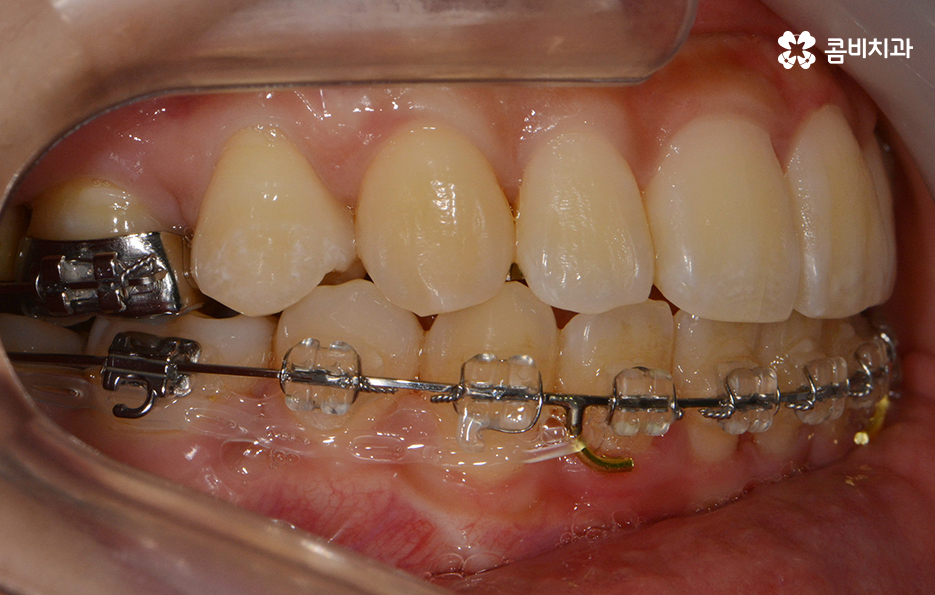

교정 치료 진행과정의 경과 모습

초기에 시술이 진행된 모습에 비해서 윗니가 가지런해졌고

돌출되었던 치아가 안쪽으로 많이 들어온 모습입니다.

발치를 했던 부위가 어딘지 잘 모를 정도로

윗니가 안쪽으로 들어와서 가지런하게

치열이 자리 잡고 있는 모습입니다.